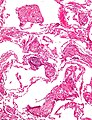

Microscopic

Features:[2]

- Dilated capillaries.

- Blood in airspace, focal.

- Plasma proteins in airspace - light pink acellular junk.

- +/-Hemosiderin-laden macrophages (known as heart failure cells in this context).

DDx:

- Pulmonary alveolar proteinosis.

- Pulmonary hemorrhage - abundant blood.